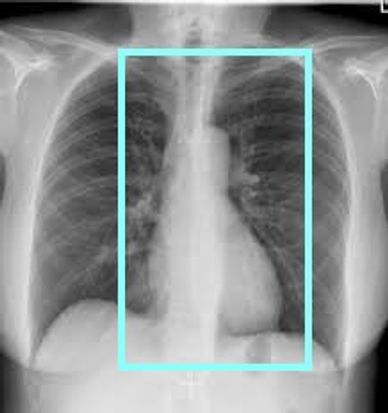

ONCE IV HAS BEEN PLACED, POSITION PATIENT WITH BOTH ARMS UP AND PERFORM A ROUTINE CARDIAC CALCIUM SCORE. REMEMBER TO KEEP YOU FIELD-OF-VIEW (FOV) TO 25CM FOR GE OR 250MM FOR SIEMENS

A FOV OF 25(GE) 250(SIEMENS) IS REQUIRED FOR SOFTWARE TO POST PROCESS